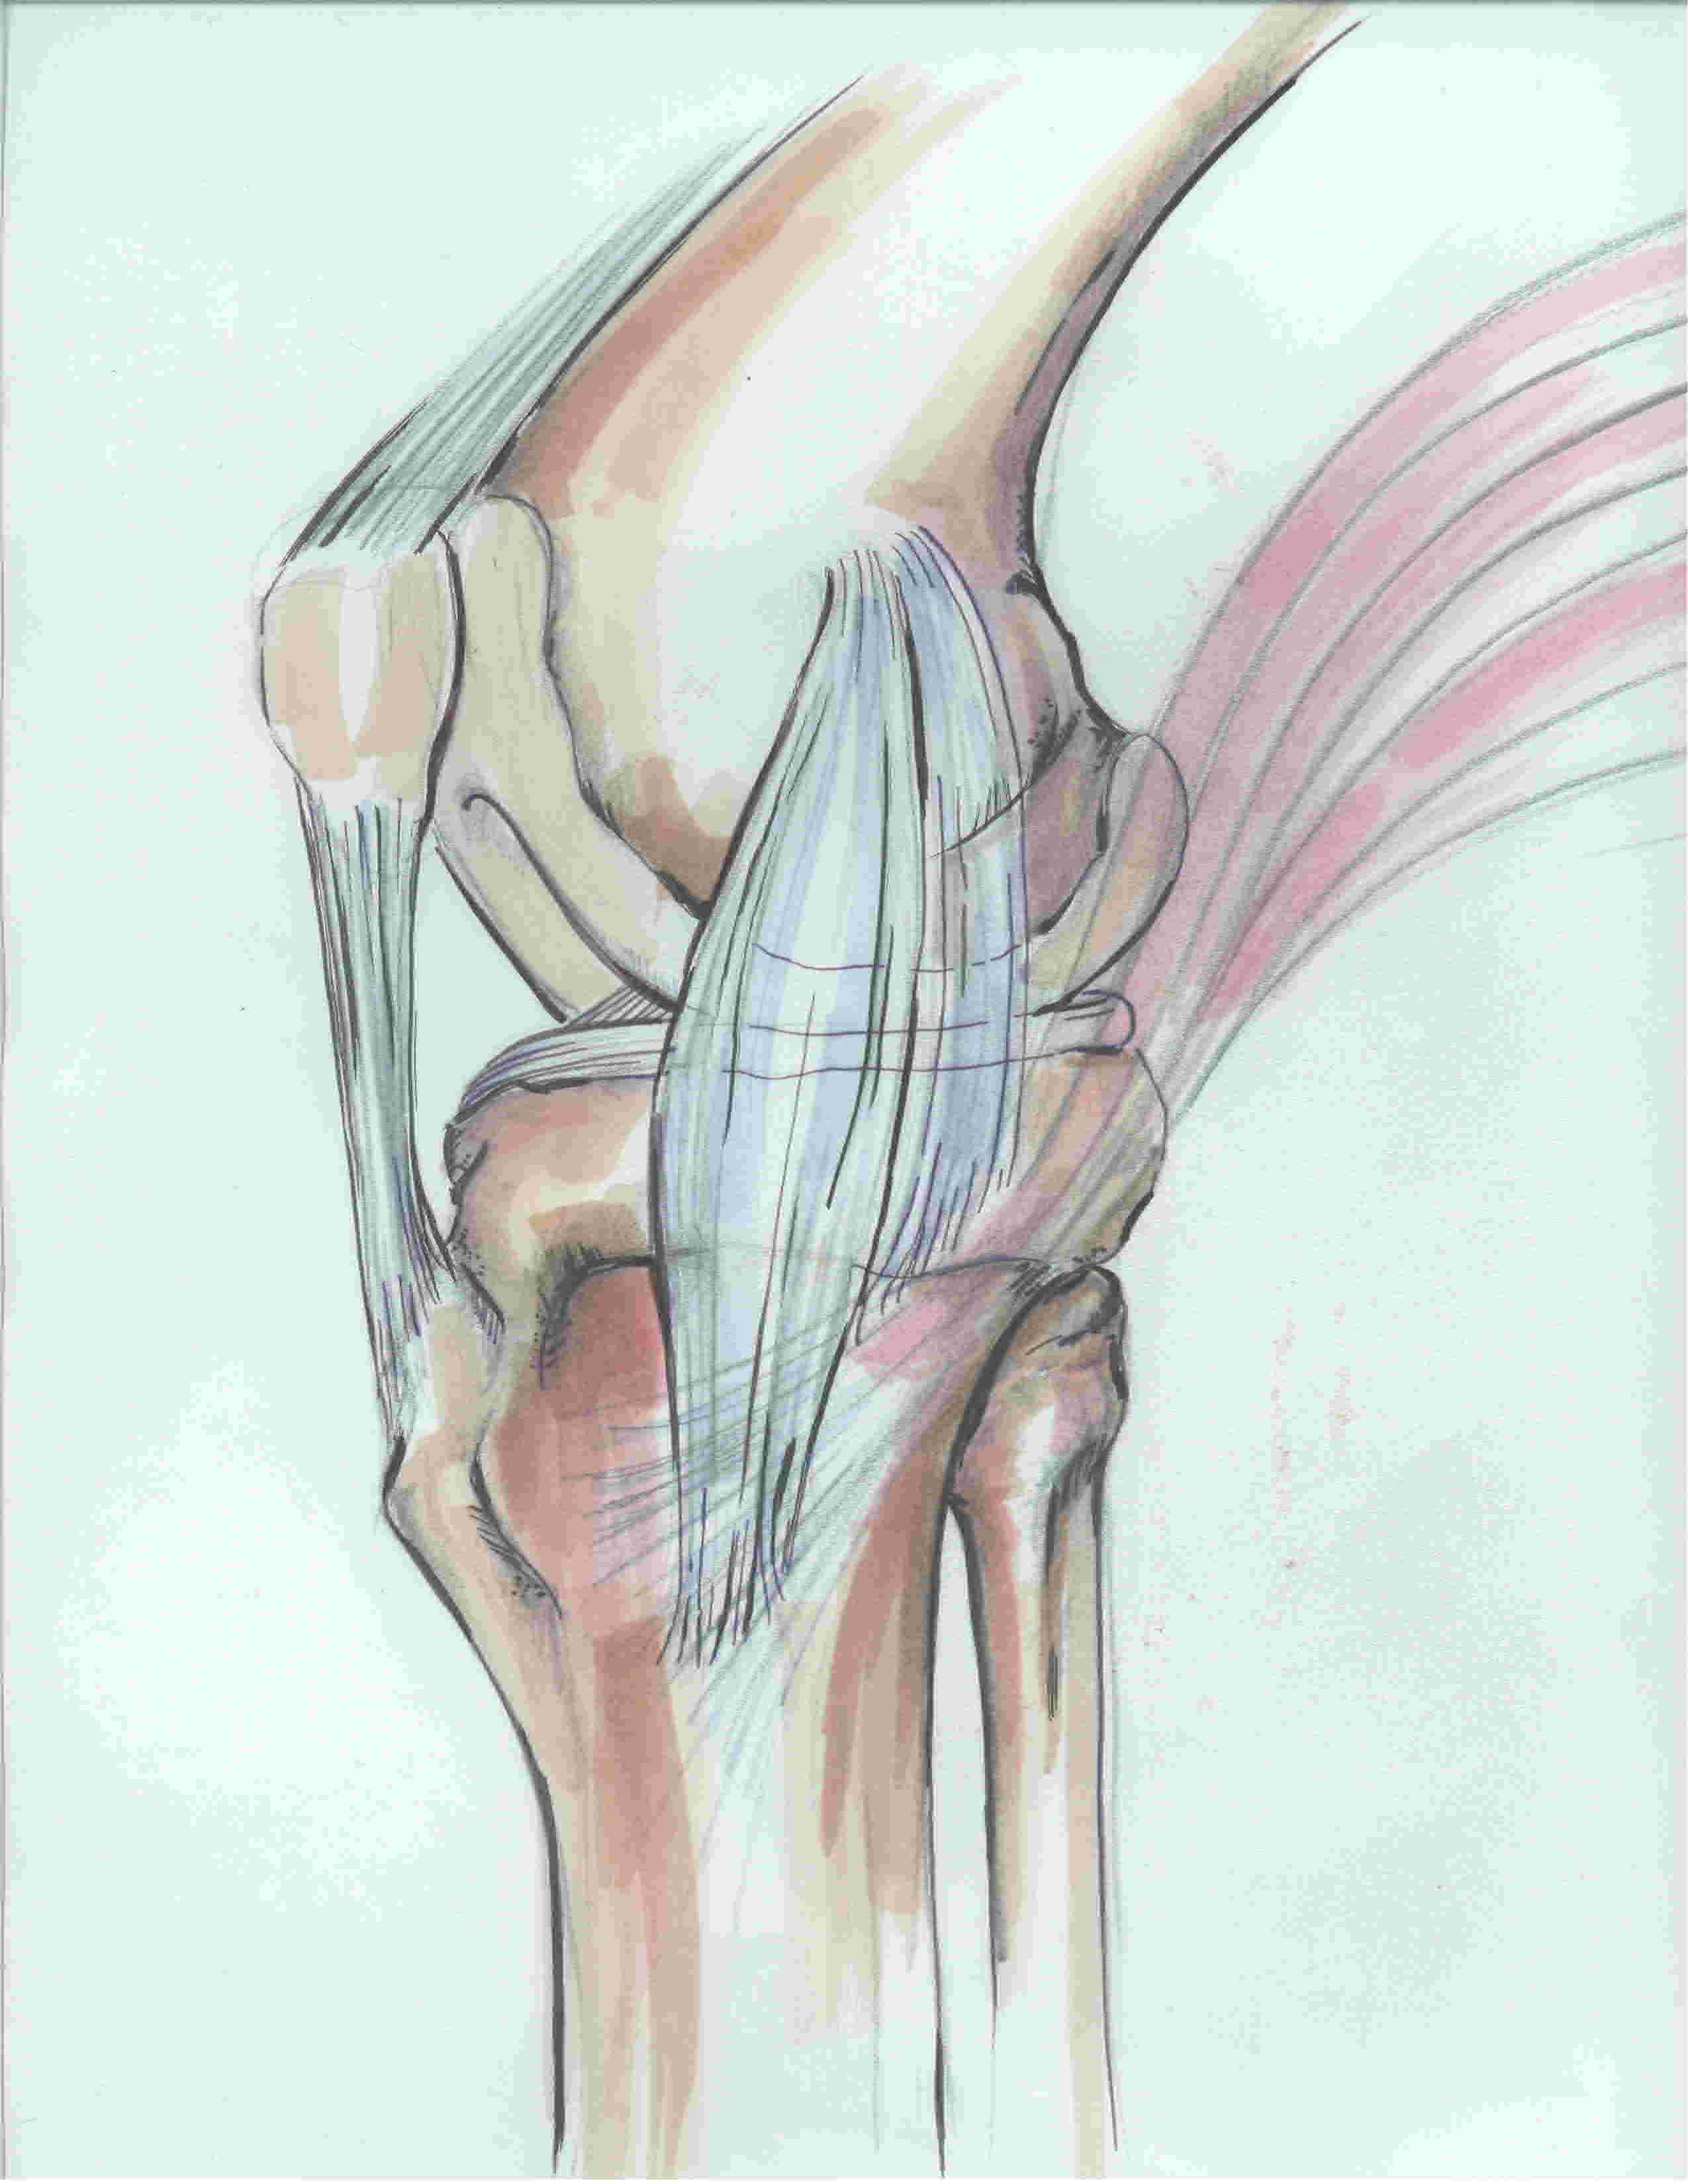

2. MCL

| Superficial MCL | Deep MCL |

|---|---|

|

Triangular in shape Origin: 3 mm proximal and 5 mm posterior to the epicondyle Insertion: 6 cm distal to the joint line onto posteromedial tibia, deep to pes anserinus Anterior margin free |

Deep to MCL Origin: inferior to medial epicondyle Insertion: 1 cm below joint line Meniscofemoral and meniscotibial ligaments - capsular thickening |

3. Posteromedial corner (5 components)

i) Posterior oblique ligament (POL)

- behind / posterior the superficial MCL

- origin: femur posterior and distal to adductor tubercle

- insertion: central arm onto posterior tibia below articular surface and the posteromedial capsule

ii) Semimembranosus

- attaches to the posteromedial corner of the tibia just below the joint line

- also has extensions blending with POL and OPL

- important dynamic stabiliser

iii) Oblique Popliteal Ligament (OPL)

- extension of semimembranosus

- extents laterally towards lateral femoral condyle

- thickens posteromedial capsule

iv) posteromedial joint capsule

v) Posterior horn of medial meniscus